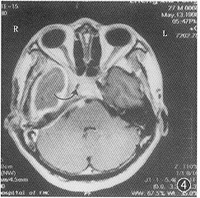

图2 1998年5月(出院7个月确诊)MRI冠状位增强。↑示HCP广泛扩展到右侧颅中窝底及小脑幕,E示颞叶水肿区

出院7个月后,1998年4月,出现精神异常,时而安静,时而烦躁打骂亲人,曾送精神病院治疗未见好转。1998年5月13日来院复查。除精神症状外,一般情况良好。MRI颅脑横断面、冠状及矢状位扫描并增强显示:右中颅窝底硬脑膜、右侧小脑幕均见明显强化的带状影,右侧颞叶水肿,局部脑沟消失(图2);右侧脑室颞角受压变小(图3);右侧海绵窦影明显增大,增厚的窦壁使颈内动脉受压变细(图4)。根据MRI所见及临床症状确诊为弥漫性肥厚性硬脑膜炎伴右颞叶水肿及器质性精神障碍。每天青霉素静脉点滴10 000 000 U共26 d,临床症状消失。1999年8月28日(15个月后)复查 MRI,颞叶水肿消退,沟回重现,侧脑室颞角恢复正常(图5),肥厚的硬脑膜因已纤维化,故不再强化,但右侧颈内动脉仍受压(图6),2000年4月(23个月后)电话询问,患者工作、生活良好,并已成婚。